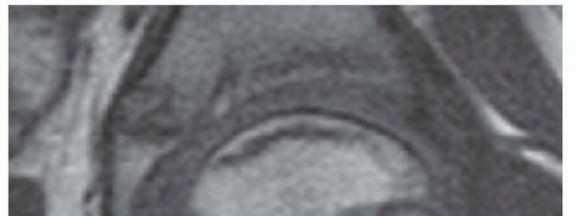

In the early stage, synovitis is observed, collapse and deformity of the cartilage of the epiphysis is usually clearly visible, and the degree of hinged subluxation (impingement) can be determined (

FIG 3

).18

FIG 3 • Magnetic resonance image of the hip of a patient with Perthes disease showing lateral subluxation, synovitis, and acetabular-femoral impingement (hinged subluxation).